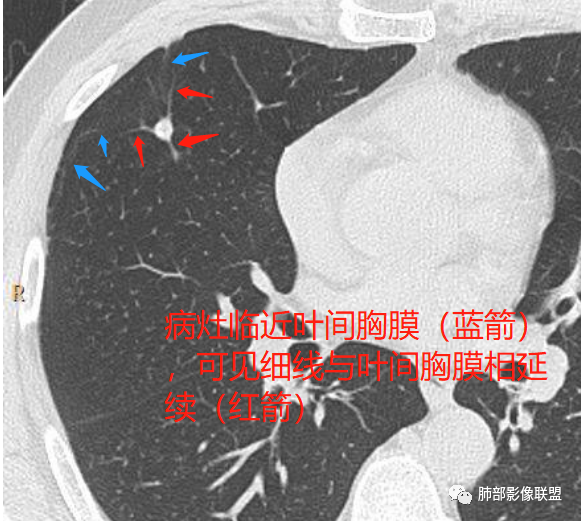

2、病灶边缘多平直,大部分呈三角形,部分呈椭圆形;

3、病灶边缘见一条或数条细线与胸膜相连。

如图所示:

长径均小于12mm。典型的形状为三角形,也可以为梭形、圆形或椭圆形。诊断的关键在于见到1-5条细线与胸膜、叶间胸膜或静脉相连,有时状如坐落于电路板的“二极管”,但以薄层CT显示为佳。有作者病理对照线状影为小叶间隔,有作者病理对照为淋巴管。其实不矛盾,因为淋巴管走行于小叶间隔内。

诊断肺内淋巴结最关键指出在于薄层扫描见到细线状影与胸膜、叶间胸膜及肺静脉相连。